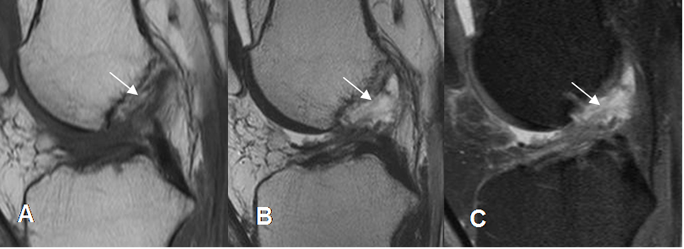

Fig 107. Ruptura parcial del LCA.

A: RM sagital en T1, B: RM sagital en T2 y C: RM sagital en STIR. Pérdida del patrón fibrilar, con ruptura de algunas fibras en el tercio medio del LCA (Flechas), por ruptura parcial.